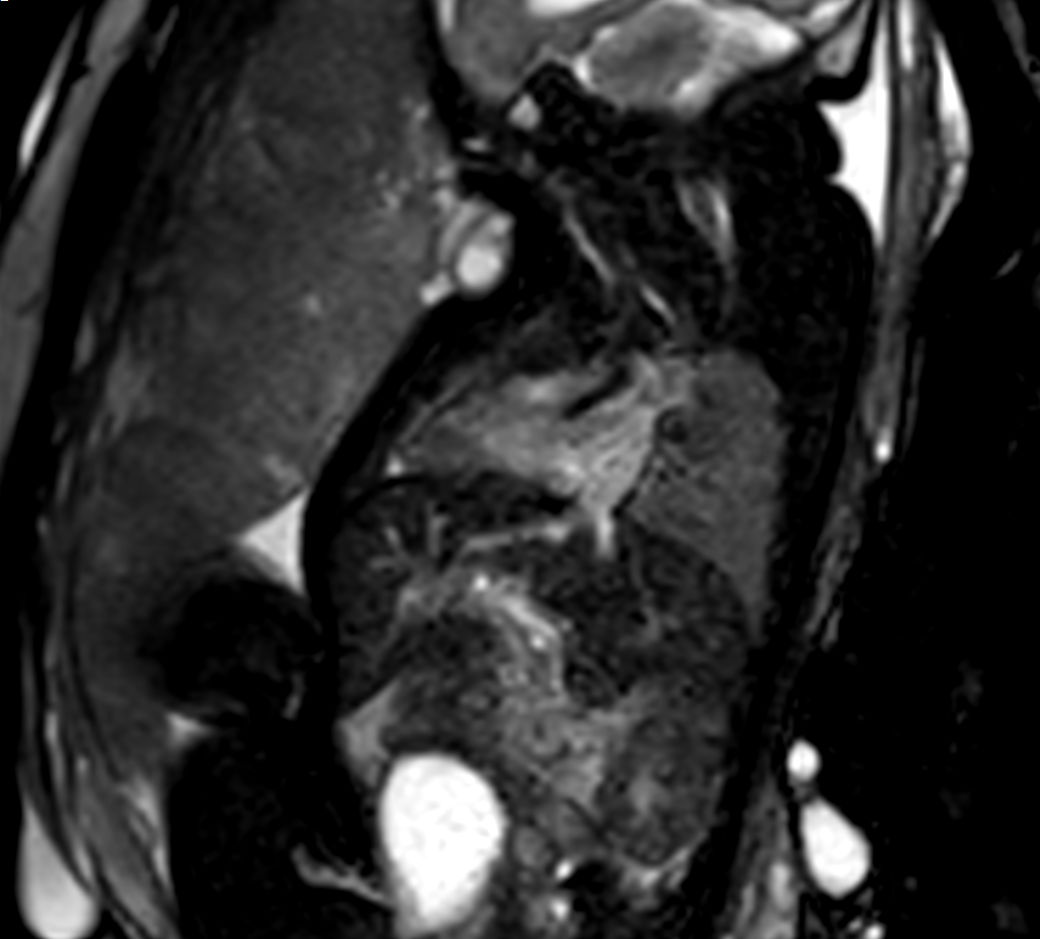

Cine bTFE 4ch

Cine bTFE 4ch - High resolution